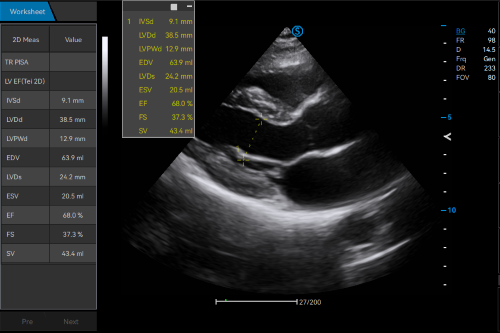

· Real-time Worksheet Display

· Cross-mode Measurement